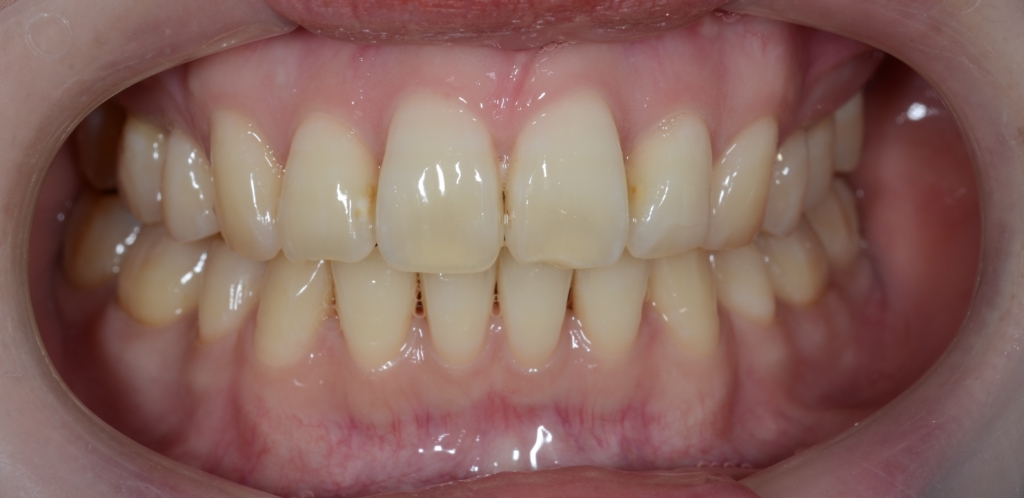

【After】

【保定】 上下ともフィックスタイプ&クリアリテーナー

【治療期間】 3年2カ月間

【治療費用】 87万6千円

【治療装置】 ハーフホワイトtypeのマルチブラケットシステム、

アンカースクリューを計4本

PLAS & パラタルバー

今回も、色々ありましたが、口元も笑顔も良い方向へ大きく変えることが出来ました。

矯正治療に伴い笑顔や横顔、口元の雰囲気はガラリと変わり、満足してもらえたようで何よりでした。

では、矯正治療前後の「レントゲン写真」や「笑顔、口元の写真」などを比較してみましょう。

次は、笑顔や横顔・口元の比較です。

左側が矯正治療前、右側が矯正治療後

イメージの違いは一目瞭然ですね!